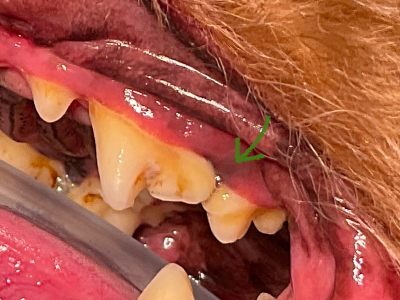

術前

矢印の歯肉の色が悪くなんだか怪しい…